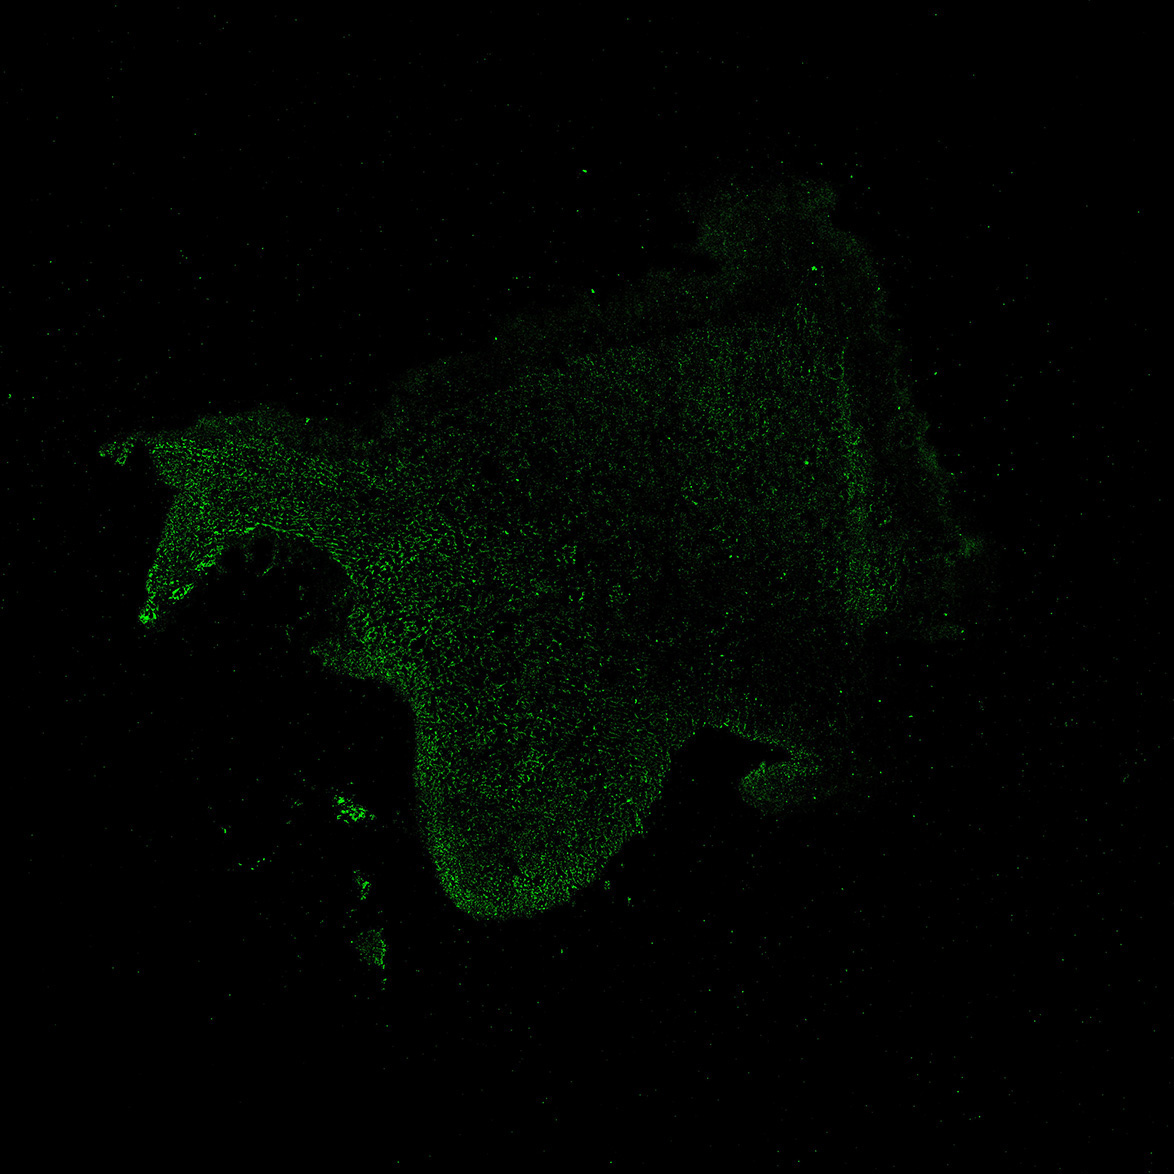

An anatomical analysis of the developing human midbrain from 6 post-conceptional weeks (PCW) to 22 PCW reveals increased tissue complexity, characterized by the emergence of dopaminergic nuclei, as highlighted by immunofluorescence analysis for tyrosine hydroxylase (TH).

11PCW

MAP2

11PCW human midbrain